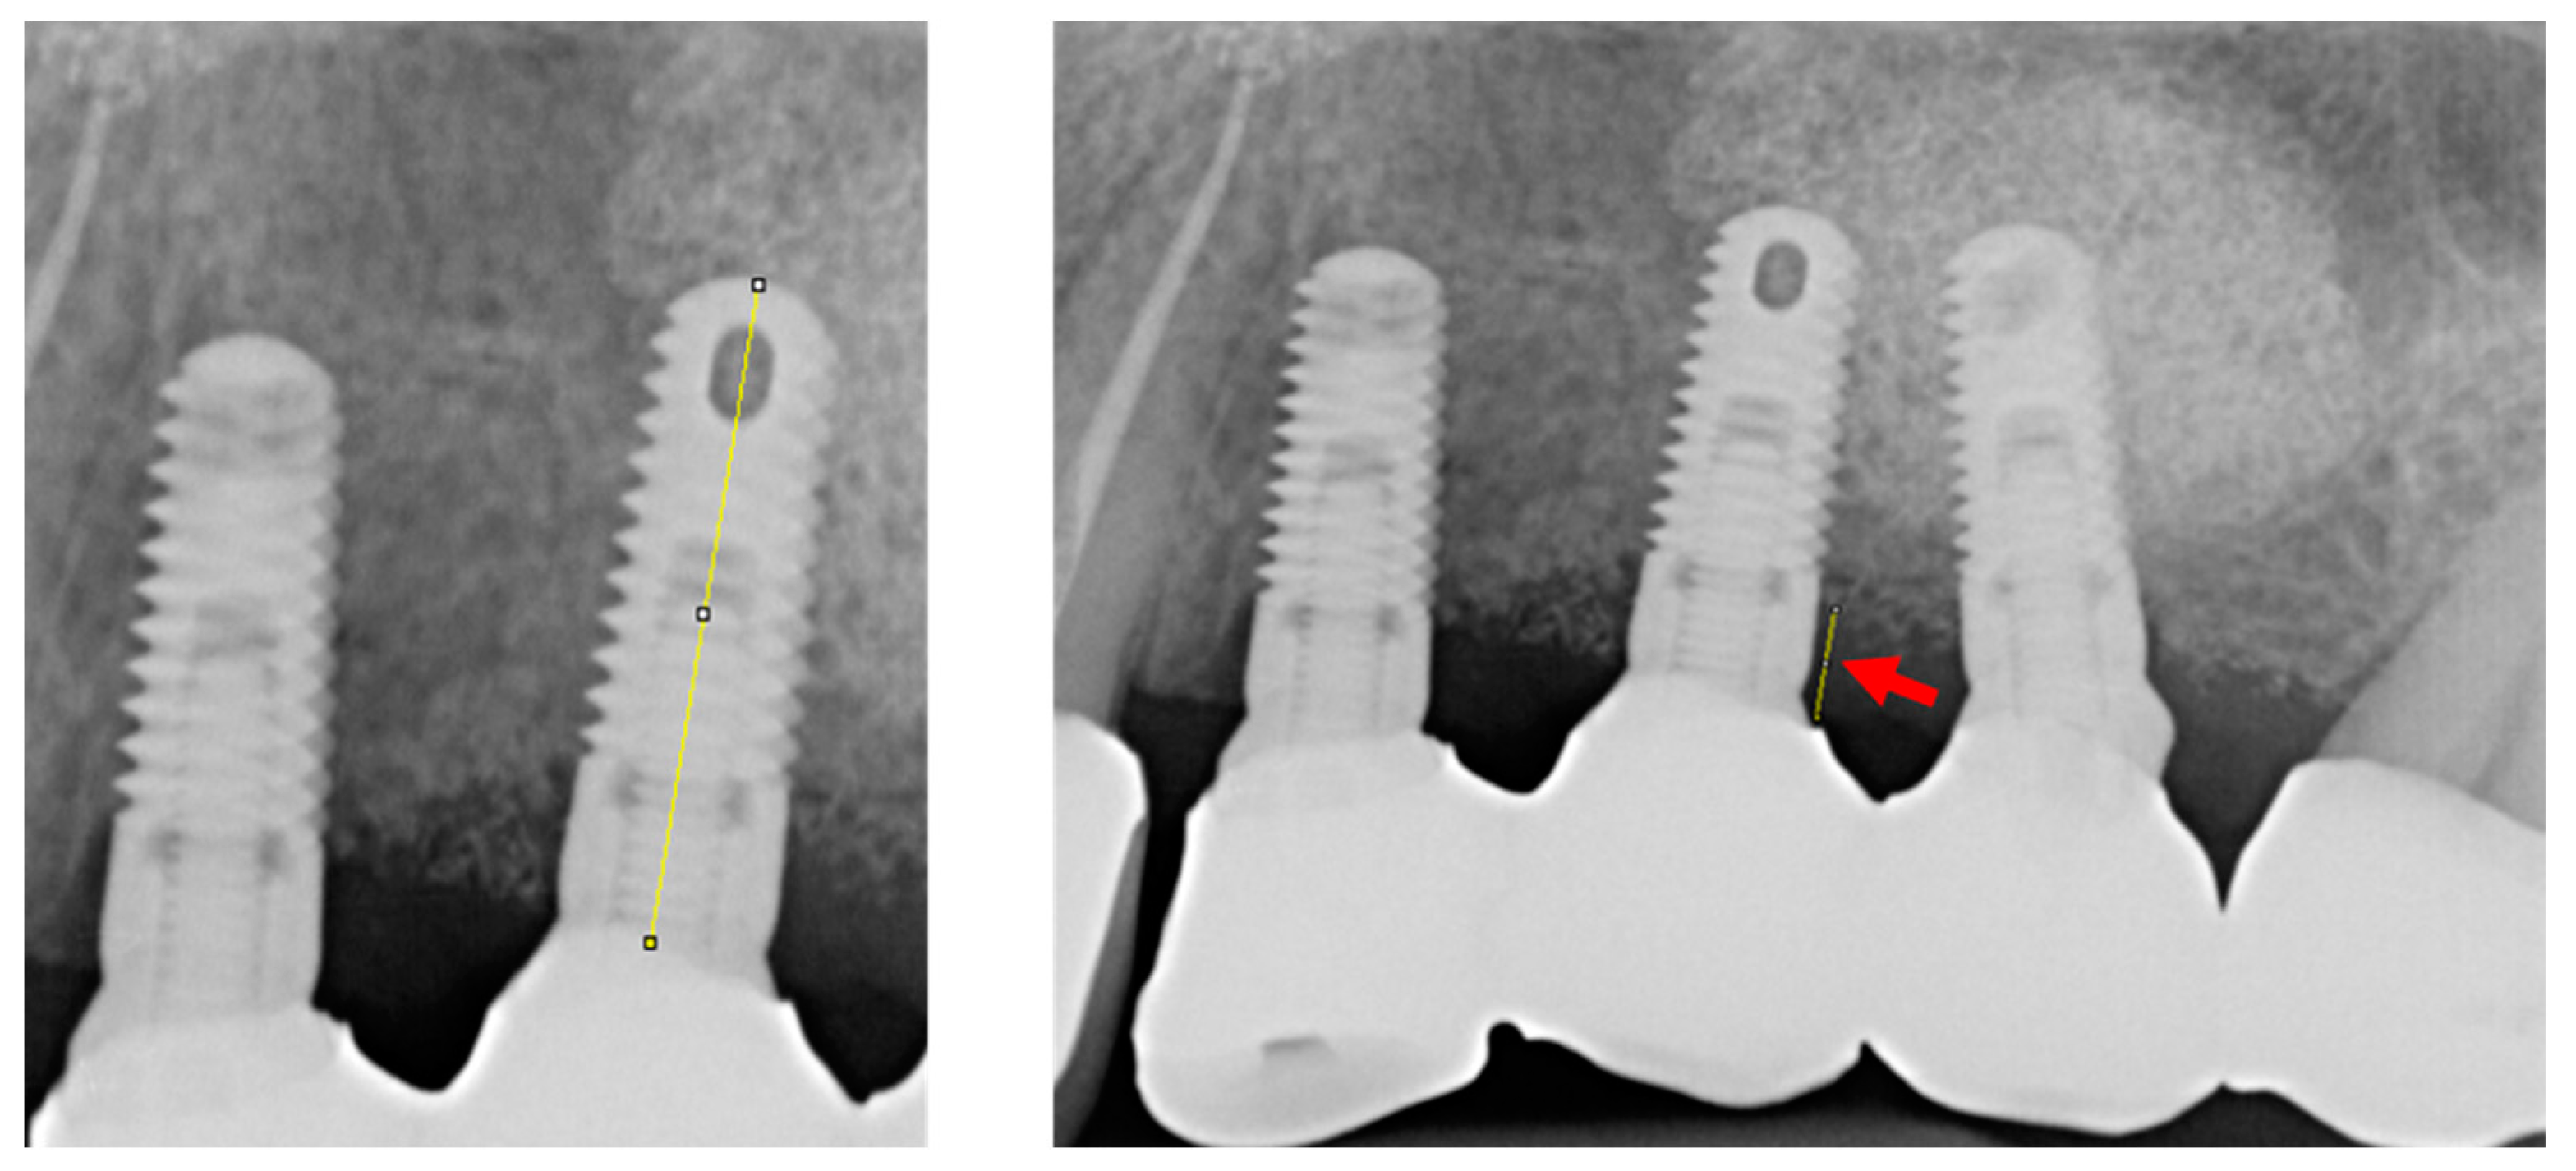

2.4. Implant Success and Peri-Implant Marginal Bone Loss

| 5 | 43 | F | 36 | 1.9 | 18.83 | 4.40 | 5 | 4.6 | 11.5 | 5.4 | 1.5 (failed) |